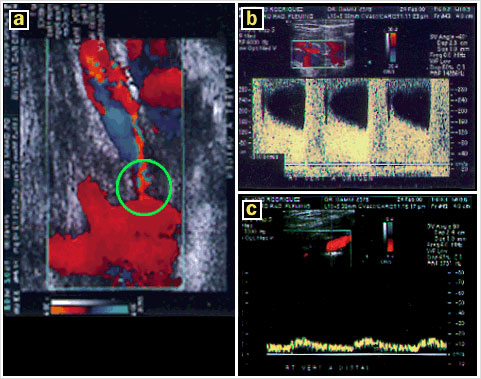

Un Eco Duplex complementario (Figura 4) confirma la estenosis de la vertebral derecha (a), que genera un elevada velocidad sistólica (b), con marcada disminución del flujo distal (c).

Eco Duplex complementario.